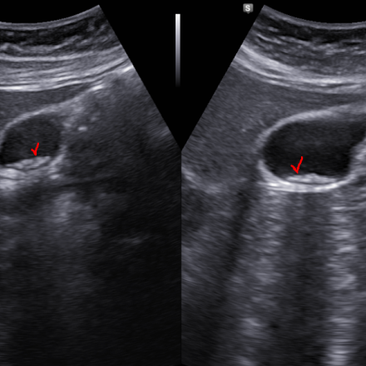

복부, 신장초음파; 흡연자에서 우연히 발견된 신장암 의증, bosniak 3

https://blog.naver.com/ejercicio/220844269712 동대문구 답십리 우리안애, 우리안愛 내과, 초음파 클리닉, 영상의학 클리닉, 내과 전문의 전병연 #동대문구내과 #성동구내과 #광진구내과 #답십리역 #장안평역 #용답역 #청량리역 #신답역 #한양대역 #왕십리역 #답십리사거리 #촬영소사거리 #전농동사거리 #내과 #국가검진 #위내시경 #대장내시경 #갑상선초음파 #복부초음파 #경동맥초음파 #심장초음파 #암검진 #래미안위브아파트 #엘림스퀘어 #두산아파트 #동아아파트 #한양아파트 #동답한신아파트 #두산위브아파트 #힐스테이트청계아파트 #래미안미드카운티 #청솔우성 #래미안크레시티 #롯데캐슬노블레스 #e편한세상답십리아르테포레